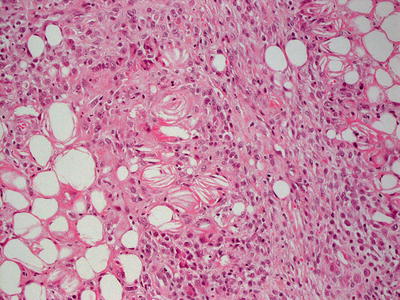

Erythema nodosum is a septal panniculitis [1]. Early lesions demonstrate septal edema and a mixed inflammatory infiltrate of neutrophils, lymphocytes, eosinophils, and occasional giant cells (Fig. 9.1). As the lesions develop, neutrophils diminish in number with increased number of histiocytes, including multinucleated giant cells (Figs. 9.2 and 9.3). Small granulomatous foci are present in some cases. The septa become thickened and fibrotic, and septal edema is less apparent. The inflammatory infiltrate may extend into the periphery of the fatty lobules, although fat necrosis is not seen. The blood vessels are not inflamed. The overlying epidermis and dermis are usually relatively unremarkable.

Fig. 9.3

Small foci that resemble granulomas, known as Miescher’s radial granulomas , are seen in the fibrous septa in some cases of erythema nodosum